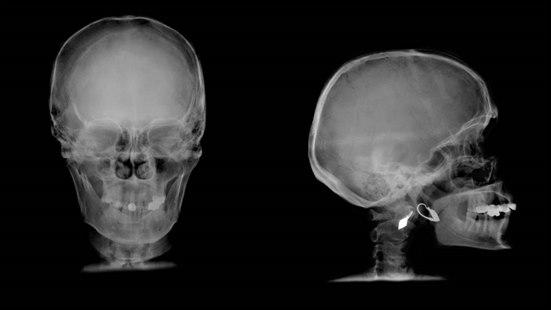

Mistenk alltid en nakkeskade (ryggmargsskade) hos en person som har pådratt seg en kraftig hodeskade. Illustrasjonsbilde: Colourbox

- Mistenk dessuten alltid en nakkeskade hos en person med en større hodeskade